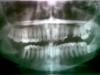

Tami Опубликовано 2 марта, 2008 Автор Поделиться Опубликовано 2 марта, 2008 Вот, если можно, пока выкладываю последний снимок. Качество, конечно, не очень, но через мобильный по другому не выйдет (поэтому несколько вариантов).Не зря ли я все-таки переживаю и еду доктора мучить? Ссылка на комментарий

Doc Опубликовано 2 марта, 2008 Поделиться Опубликовано 2 марта, 2008 Ну вот, никто ничего не говорит... Жаль... До похода еще ждать и ждать, а болеть-болит... По таким снимкам вообще ничего сказать нельзя. Потому никто и не говорит. Единственное, что можно сказать, это то, что нужно будет еще две восьмерки удалять, а верхняя очень удобно лежит как раз на гайморовой, а возможно даже и в ней, потому придется искать очень опытного хирурга, либо удалять в стационаре. И еще там мелкий прикольненький девятый зуб над ней, если не ошибаюсь. Ссылка на комментарий

Bier Опубликовано 3 марта, 2008 Поделиться Опубликовано 3 марта, 2008 А чем снимок плох? Он в принципе плох или в смысле такое качество на компе?2 РВК на верхней челюсти справа, там же где пятерка удалена. К доктору записалась на завтра. А претензий у меня и в мыслях не было, я наоборот ему очень благодарна... Я же пойти хочу не чтобы претензии предъявить, а просто вдруг не должно до сих пор болеть, может что-то делать надо... Только даже если это из-за того, что пазуху проткнули (кстати, вот эта сторона как раз черная), я думаю, это же наверное не к стоматологу, а к лору... Вот потому и сомневаюсь... А к стоматологу я из-за того, что болит по десне на эти три зуба - 4, бывший 5, 6. Я боюсь, вдруг там опять эти кисты начали образовываться...я думаю, что плохое качество фотографии, у вас по всей видимости электронно-лучевой монитор? тогда на фоне окна снимок сфоткайте. Вы сфотографировали снимок в перевернутом виде, ваше право должно быть на снимке слева.пазуха и должна быть на снимке темная (т.к. в норме в ней ничего нет). Ну вот чтобы претензий не было и в дальнейшем, надо сходить к врачу сейчас. З.Ы. восьмерки надо удалять, в стационаре все можно сделать и под наркозом и без хамства, вопрос личной договоренности и адекватной оплаты. Ссылка на комментарий